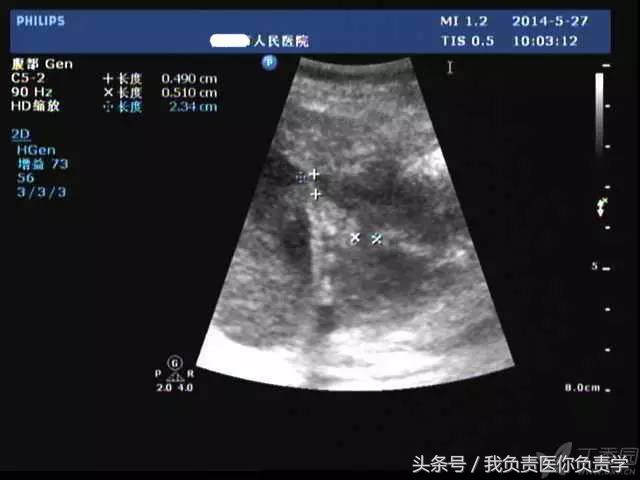

典型病例 5

(由丁香园注册用户「ouchen2010」提供)

患者女,75岁,右上腹疼痛就诊。查体示右上腹压痛明显,无明显腹膜炎体征。

超声检查发现胆囊内可见沉积物及结石回声,胆囊近底部可见 0.5cm 回声中断,十二指肠亦可见 0.5cm 回声中断,二者间见 5.8×4.4cm 混合性团块。

图1示胆囊饱满,内透声差,可见沉积物回声

图2示胆囊、胃窦及十二指肠之间可见混合回声型团块

图3-图5为胆囊局部放大图像,显示胆囊囊壁局部回声中断,周围可见不规则混合回声团块

图6和7为相应CT表现

术后诊断为慢性结石性胆囊炎,胆囊-十二指肠穿孔并内瘘形成。